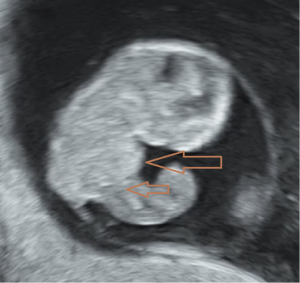

Chief complaint: a 27-year-old gravida presented for routine prenatal ultrasonographic evaluation. Early first-trimester ultrasound surveillance (6 weeks) revealed unremarkable fetal development. The patient denied any pregnancy-associated discomfort at this stage. History: bilateral salpingectomy performed. Personal and family history: the patient had no significant family or genetic history. Physical examination revealed no remarkable findings. All laboratory parameters fell within established normal limits. The patient used ART due to tubal factors. On 16 June 2024, the patient underwent a frozen-thawed blastocyst transfer. The two-dimensional (2D) ultrasound examination at 6 weeks of pregnancy showed a gestational sac in the uterine cavity, with a yolk sac inside and a 0.52 cm-long fetal bud close to the yolk sac, which showed a faint primitive heart tube pulsation. Ultrasound examination at 8 weeks of pregnancy showed a gestational sac in the uterine cavity, with one yolk sac, an amniotic sac, and two fetuses in the gestational sac. One fetus had a crown-rump length of 2.03 cm, and the other fetus had a crown-rump length of 1.88 cm. Both fetuses were consistent with an 8-week pregnancy. Both fetuses demonstrated complete thoracic ectopia cordis with anterior protrusion and cardiac fusion. The sagittal section showed that the two fetuses had a “ball-holding” sign, with a common heartbeat of 169 bpm (Figure 1). The organs above the umbilical part of the two fetuses were connected and protruded towards the front of the abdomen, with a cover on the surface. The cross-section of the chest showed that the two fetuses showed a “dumbbell” sign (Figure 2). The umbilical cords of the two fetuses were fused into a thick umbilical cord, and the entrance end of the umbilical cord abdominal wall was inserted into the fusion of the umbilical cord. The distal end of the umbilical cord was bifurcated and inserted into the placental parenchyma, respectively. Three-dimensional (3D) ultrasound surface imaging intuitively showed the relative positional relationship between the two fetuses and the exposure of the conjoined twins to the heart that fused each other on the outside of the chest cavity (Figure 3). Due to the early gestational week, the anterior diaphragmatic midline of the two fetuses was unclear. The ultrasound machine used in this case was a GE Voluson E10 (GE Healthcare, Chicago, IL, USA), with a RIC5-9-D probe. Figures 4,5 show normal fetus control images at the same gestational age.

With the widespread application of high-resolution transvaginal ultrasound, visualization of early pregnancy has become possible. The accuracy of assessing the risk of fetal chromosomal abnormalities through early pregnancy ultrasound combined with biochemical markers has improved, leading to the diagnosis of more fetal abnormalities in the early stages of pregnancy. A study indicated that ultrasound diagnosis of conjoined twins typically occurs between 11 and 13 weeks and 6 days. Screening at this stage can detect the most severe fetal malformations (8). There are reports that high-resolution ultrasound has advanced the diagnosis of conjoined twins to 7 weeks of gestation. However, due to the early gestational age, it is difficult to precisely determine the specific type of connection between the twins, and color Doppler ultrasound is typically required to assist in diagnosing the presence of conjoined twins (9). Fetal development is a process, and it can only be detected by ultrasound once it has reached a distinguishable gestational age. When fetal activity increases, around 8 weeks of gestation, it becomes easier to distinguish between monochorionic twins and conjoined twins (10). The patient underwent an ultrasound examination at 6 weeks of gestation, during which only a small, short, line-like embryonic bud and weak fetal heartbeat were observed. During the ultrasound examination at 8 weeks of gestation, we discovered that the two fetuses were embracing a “spherical” structure. The sagittal section revealed the “ball-holding” sign, and the transverse section showed a notch at the junction of the thoracic and abdominal walls, presenting the “dumbbell” sign. These two signs are specific to thoracoabdominal conjoined twins, with both fetuses affected by Cantrell’s pentalogy. Transvaginal 2D and 3D ultrasound provides direct evidence for the early identification of a special type of conjoined twins and advances the diagnostic gestational age to 8 weeks. Through transvaginal 2D ultrasound, the issue was identified, followed by adjusting the probe direction and angle to locate the specific connection site of the conjoined twins and determine the type of connection. The multiplanar views of 3D ultrasound provide additional detailed information. Adjusting the direction of light incidence, rotating the probe at multiple angles, and adjusting the 3D image, combined with surface imaging mode, yields more detailed features. The combination of 2D and 3D ultrasound provides more information than 2D ultrasound alone, offering more intuitive images, particularly suitable for fetuses with abnormal external features. A study has confirmed the role of 3D ultrasound in diagnosing prenatal abnormalities, which is consistent with our findings (11).

In summary, conjoined twins with bilateral Cantrell’s pentalogy likely represent the most severe phenotypic manifestation with the poorest prognosis. The characteristic “ball-holding” and “dumbbell” signs on ultrasonography serve as pathognomonic indicators of this condition in monochorionic monoamniotic twins. Early recognition of these sonographic markers is critical for timely diagnosis and management.